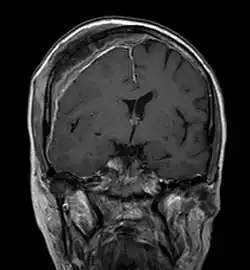

Magnetresonanztomografie

Mit der Magnetresonanztomografie (MRT) können insbesondere Weichteilgewebe gut bildmäßig dargestellt werden. Sie gilt für die Diagnostik von spinalen Metastasen (Metastasen in der Wirbelsäule) als Goldstandard. Mit der MRT können darüber hinaus weitere Komplikationen im Bereich der spinalen Metastasen, wie beispielsweise Infektionen oder Verletzungen des Bandscheiben- und Ligamentkomplexes, Knochenmarködeme nach einer frischen Fraktur,[117][118] oder Kompressionen neuraler Strukturen, sichtbar gemacht werden.[18]:16 Mit Hilfe der STIR-Sequenz (engl. short tau inversion recovery) ist es möglich, das Alter einer Fraktur zu ermitteln. Zum Aufspüren von Metastasen ist die T1-Wichtung mit Gadolinium-haltigen Kontrastmitteln, wie beispielsweise Gadotersäure, besonders gut geeignet. Das Kontrastmittel reichert sich in den Metastasen besonders stark an.[18][119]

- Vergleich CT / MRT bei osteolytischen Metastasen eines Mammakarzinoms in der Wirbelsäule

-

Sagittal rekonstruierte CT, Darstellung im Knochenfenster. Da die Patientin multiple Metastasen in allen Körperregionen hatte, konnte sie die Arme nicht für die Untersuchung nach oben nehmen, weshalb die Hände mit abgebildet sind. -

Sagittal rekonstruierte CT, Weichteilfenster. Neben den Metastasen in der Wirbelsäule, die teilweise nach hinten in den Spinalkanal einwachsen, auch Metastasen im Brustbein. Zusätzlich Lebermetastasen. -

Sagittale native T1-gewichtete MRT -

Sagittale native T1-gewichtete MRT. Deutlich sichtbar die Ausdehnung bis in die Bogenwurzeln.